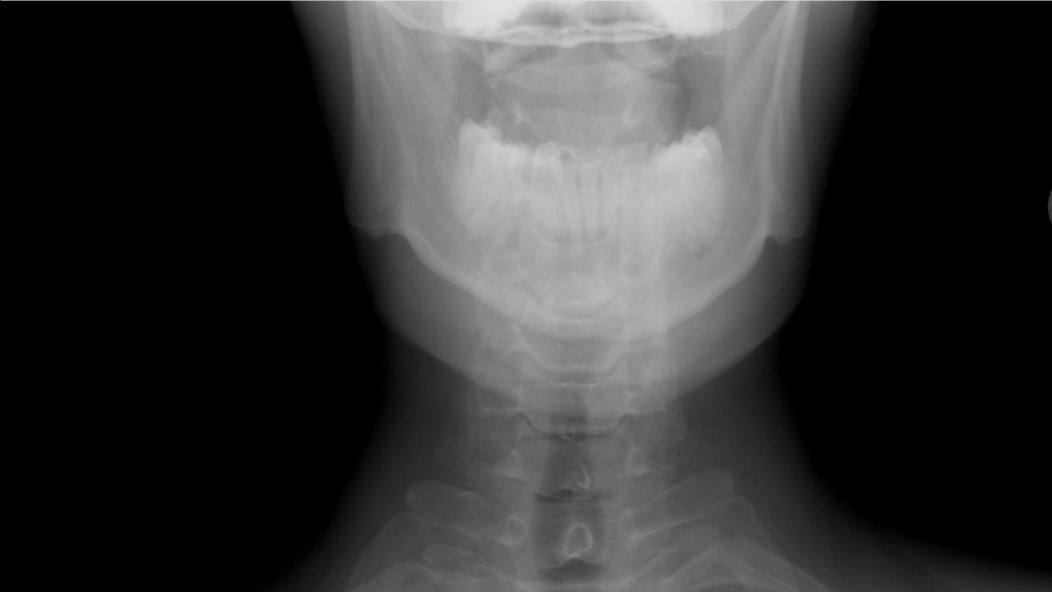

Сразу после инцидента школьница была отправлена в медпункт, где ей оказали первую помощь. Однако состояние ребенка требовало более серьезного вмешательства, и вскоре пострадавшую доставили в больницу. Врачи провели обследование и выявили компрессионные переломы трех позвонков. Это означает, что 6-класснице предстоит долгий путь к восстановлению: около полугода она будет вынуждена носить специальный корсет.